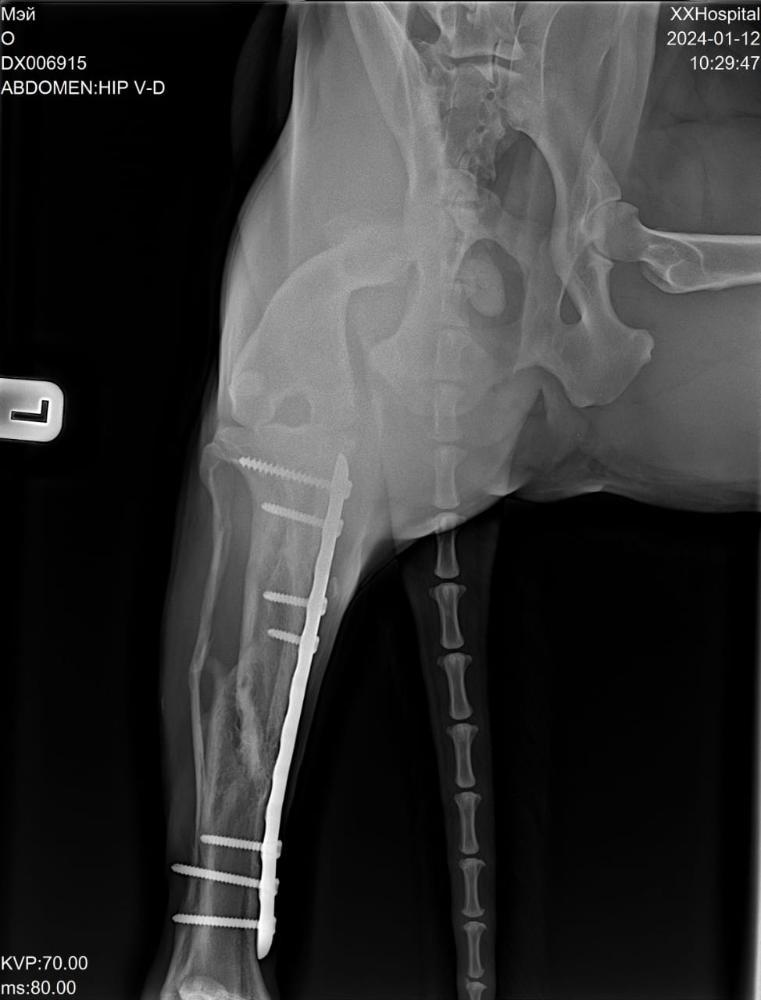

Светлана 2101 Опубликовано 12 января, 2024 Опубликовано 12 января, 2024 Сегодня съездили с Мэем к ортопеду. Сделали рентген. Сразу скажу, я осталась очень довольна приемом, содержательной беседой с врачом. Но есть новости хорошие и не очень. Сделано - рентген грудной и поясничный отдел, тазобедренных суставов и рентген оперированной лапы. По позвоночнику - в прекрасном состоянии, нет признаков травмы и дегенеративных изменений, кроме единичного незначимого очага дискоспондилита в среднем грудном отделе. На одном позвонке только есть изменения ( на снимке красным). Это ни о чем .Никак на жизнь не влияет. Тазобедренные суставы в отличном состоянии, без признаков дисплазии. В оперированной лапе - конструкция стабильна, признаки консолидации отломков. То есть всё хорошо. Доктор сказал, что далее ещё больше укрепляться будет. Процесс нарастания костной мозоли ещё идёт. Новости не очень. Измерил угол наклона плато, это крепление связок. Не очень владею всеми терминами, но своими словами напишу, как поняла. Этот угол у Мэя 20°, норма 14, при значении 25 и выше сто процентов разрыв ПКС неминуем. Хоть доктор и написал в заключении, что риск разрыва ПКС невелик, но на словах мне сказал, что вероятнее всего рано или поздно связки порвутся. 20° это уже большое натяжение, рвутся и при 22-23. Соответственно, рекомендации режим спокойных прогулок в монорежиме без кучных игр для минимизации нагрузки на коленные суставы . То есть спокойный режим даже не столько для оперированной лапы, сколько угроза разрыва ПКС. По словам доктора, это генетическая предрасположенность. В беседе он так сказал, что, да вы можете стараться его ограничивать от прыжков, но один раз он не прыгнет, а в другой раз всё равно прыгнет. Теперь вы знаете, что можно ожидать, но совсем собаку не ограничить во всем. А Мэй как раз очень прыгучий. Он даже на подзыв не просто подбегает, а прыгает.И бежит он прыжками. Один плюс, что он не знает диванов, и нет этого туда-сюда по 20 раз в день. Но на улице он хочет бегать. И бегает он очень мощно.Теперь понятно, что надо помнить об этом и стараться минимизировать прыжки . Но до сих пор связки целы, а прожил он с ними уже несколько лет, и режим у него был наверняка активный, никто его не ограничивал. Есть надежда, что продержатся они и ещё. И опять здесь очень хорошо, что он на НП, натуральные коллагены и Хондроитины помогут укреплению связок и сохранят суставы и позвоночник ,которые сейчас в прекрасном состоянии . Вот такое обследование. Я очень рада, что нет проблем в позвоночнике и суставах. Но не без ложки дегтя. Всё равно спокойный режим прогулок и жизни. А там как сложится. Просто теперь мы об этом знаем, что можно ожидать . 4 3

Светлана 2101 Опубликовано 12 января, 2024 Опубликовано 12 января, 2024 Рентген грудного отдела, вот единственный позвонок с дискоспондилитом, остальные все красивые Рентген пояснично крестцового отдела. Без изменений. Рентген тазобедренные. Рентген конструкции на оперированной лапе и углы. 5